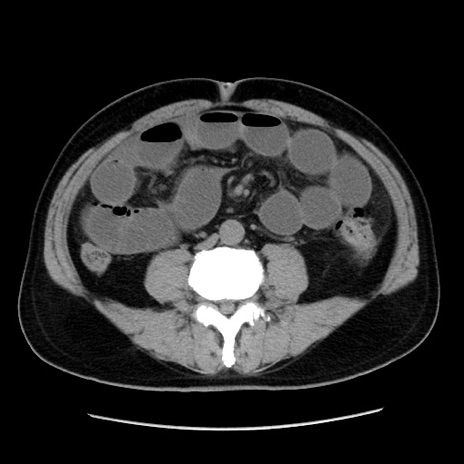

症例16(横断像)

【症例】 70歳代男性

【主訴】 腹痛、嘔吐

【現病歴】 約1ヶ月前より間欠的に腹痛と嘔吐あり、当院消化器内科を受診したところCTで多発する肝臓のLDAを指摘され、精査中であった。以降は消化器症状は安定していたが、2日前より嘔気と腹痛があり、同日より排便・排ガスが消失した。改善認めず、 本日、救急外来を受診した。

【既往歴】 大腸ポリープ切除後。

【身体所見】意識清明・会話良好、BT 36.3℃、BP 127/80mmHg、 P 80bpm、腹部:膨満あり、平坦・軟、上腹部正中および下腹部正中に圧痛あり、反跳痛なし、筋性防御なし。

【データ】WBC 7200、CRP 0.77